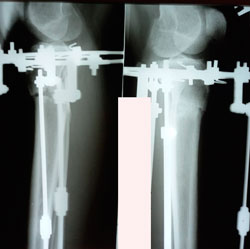

Исходник - 29 лет.

Дата операции - 29.09.2020

на фиксации

Дата снятия аппаратов 12.01.2021